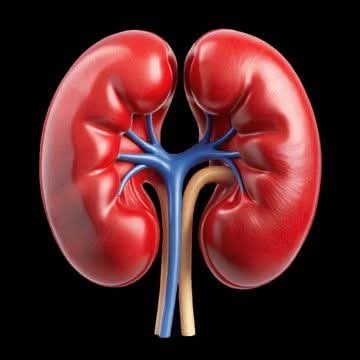

بالحديث مع الدكتور أحمد رأفت تحدث قائلا كثير من محاربي مرض الكلى يشعرون بحالة من القلق، الاضطراب، أو “عدم الارتياح” حتى في الأوقات المستقرة.. إذا كنت تمر بهذا، فاعلم أنك لست وحدك، والأهم أن هذا الشعور له أسباب طبية حقيقية وليس مجرد ضعف في الحالة النفسية.

إليك 5 أسباب طبية تجعل “القلق” عرضاً مرتبطاً بالمرض:

1. تراكم السموم (Toxins):

عندما تقل كفاءة الكلى في الفلترة، تتأثر كيمياء الدماغ ببعض الفضلات التي لم تخرج من الجسم، مما يؤدي للشعور بالارتباك والتوتر.

2. خلل المعادن والأملاح:

عدم توازن البوتاسيوم، الصوديوم، والكالسيوم يؤثر مباشرة على الإشارات العصبية والحالة المزاجية.

3. فقر الدم (الأنيميا):نقص الهيموجلوبين يعني وصول أكسجين أقل للمخ، وهذا يترجمه الجسم أحياناً على شكل “نوبات هلع” أو ضيق تنفس.

4. اضطرابات النوم:

الحاجة المتكررة للتبول ليلاً، الحكة، أو ضيق التنفس تمنع النوم العميق، مما يضع الجهاز العصبي في حالة استنفار دائم.

5. هرمونات التوتر:

الإصابة بمرض مزمن تضع الجسم طبياً في حالة “تأهب” (Stress Mode)، مما يرفع مستويات هرمونات التوتر بشكل مستمر.